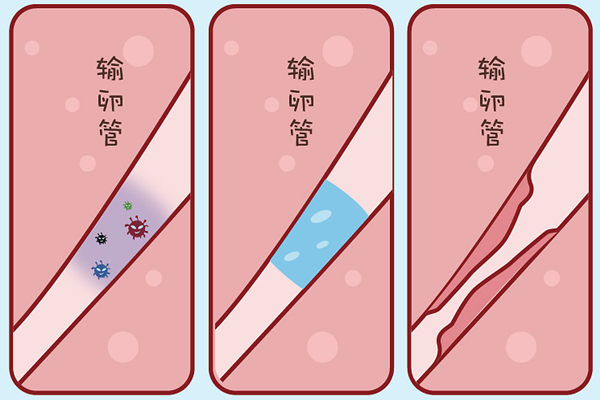

卵泡只有发育成熟才能诱发排卵,此时排出的卵子才会成熟健康且功能健全。而卵泡成熟的特征是呈圆形或椭圆形、直径达18-25mm、卵泡内呈无回声区、清亮纯净、边界清晰。若女性因卵巢疾病,如多囊卵巢综合症、下丘脑-垂体-卵巢轴功能异常或是内分泌紊乱等,导致卵泡发育不良,就会造成取卵数量降低,与前期看到的基础卵泡数量不同。

3、跑卵

若是出现跑卵,也会导致两者数目存在差异。跑卵是指在取卵手术之前就发生了排卵,从而造成了取卵数量变少。这主要是医生对卵泡发育成熟的时间掌握和排卵发生时机出现偏差所致的。